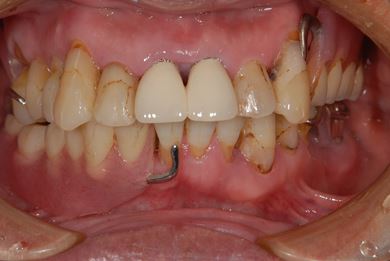

骨再生スピードインプラント治療+遊離歯肉移植

| 性別/年齢 | 男性 / 66歳 | ||||||||||||||||||||||||||||||||

| 主訴 | 入れ歯の部分をインプラントにしたい。 | ||||||||||||||||||||||||||||||||

| 治療方針 | サイナスリフトにより上顎洞を拳上し、インプラント治療を可能にする。 | ||||||||||||||||||||||||||||||||

| 治療内容 | インプラント8本(サイナスリフト、抜歯即日スピードインプラント)、ハイブリッドセラミッククラウン9本、遊離歯肉移植 | ||||||||||||||||||||||||||||||||